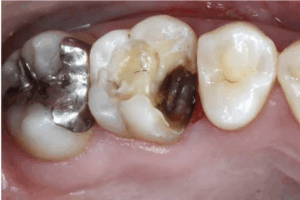

これは、本格的に進行し始めた虫歯C2(シーツー)です。

エナメル質から、象牙質にまで虫歯が進行した状態です・・・

ここから、痛みを感じたり冷たいものや甘いものがしみたりしてきます!

見た目も、誰でもわかるようなザ・虫歯!という、黒く穴が空いた状態になります。

歯医者では、虫歯部分を大きく削り白い樹脂で詰めていきます。

個人差はありますが、治療に麻酔が必要な方も出てきます。

これは、神経まで到達してしまった虫歯C3(シースリー)です。

冷たいもの、温かいものまでもひどくしみて痛みます・・・

歯が欠けてしまったり、何もしなくてもズキズキ痛みます。

歯医者では、歯の神経を取る治療がスタートします。

こうなってしまうと、二度と自分の健康な歯は戻ってきません💧